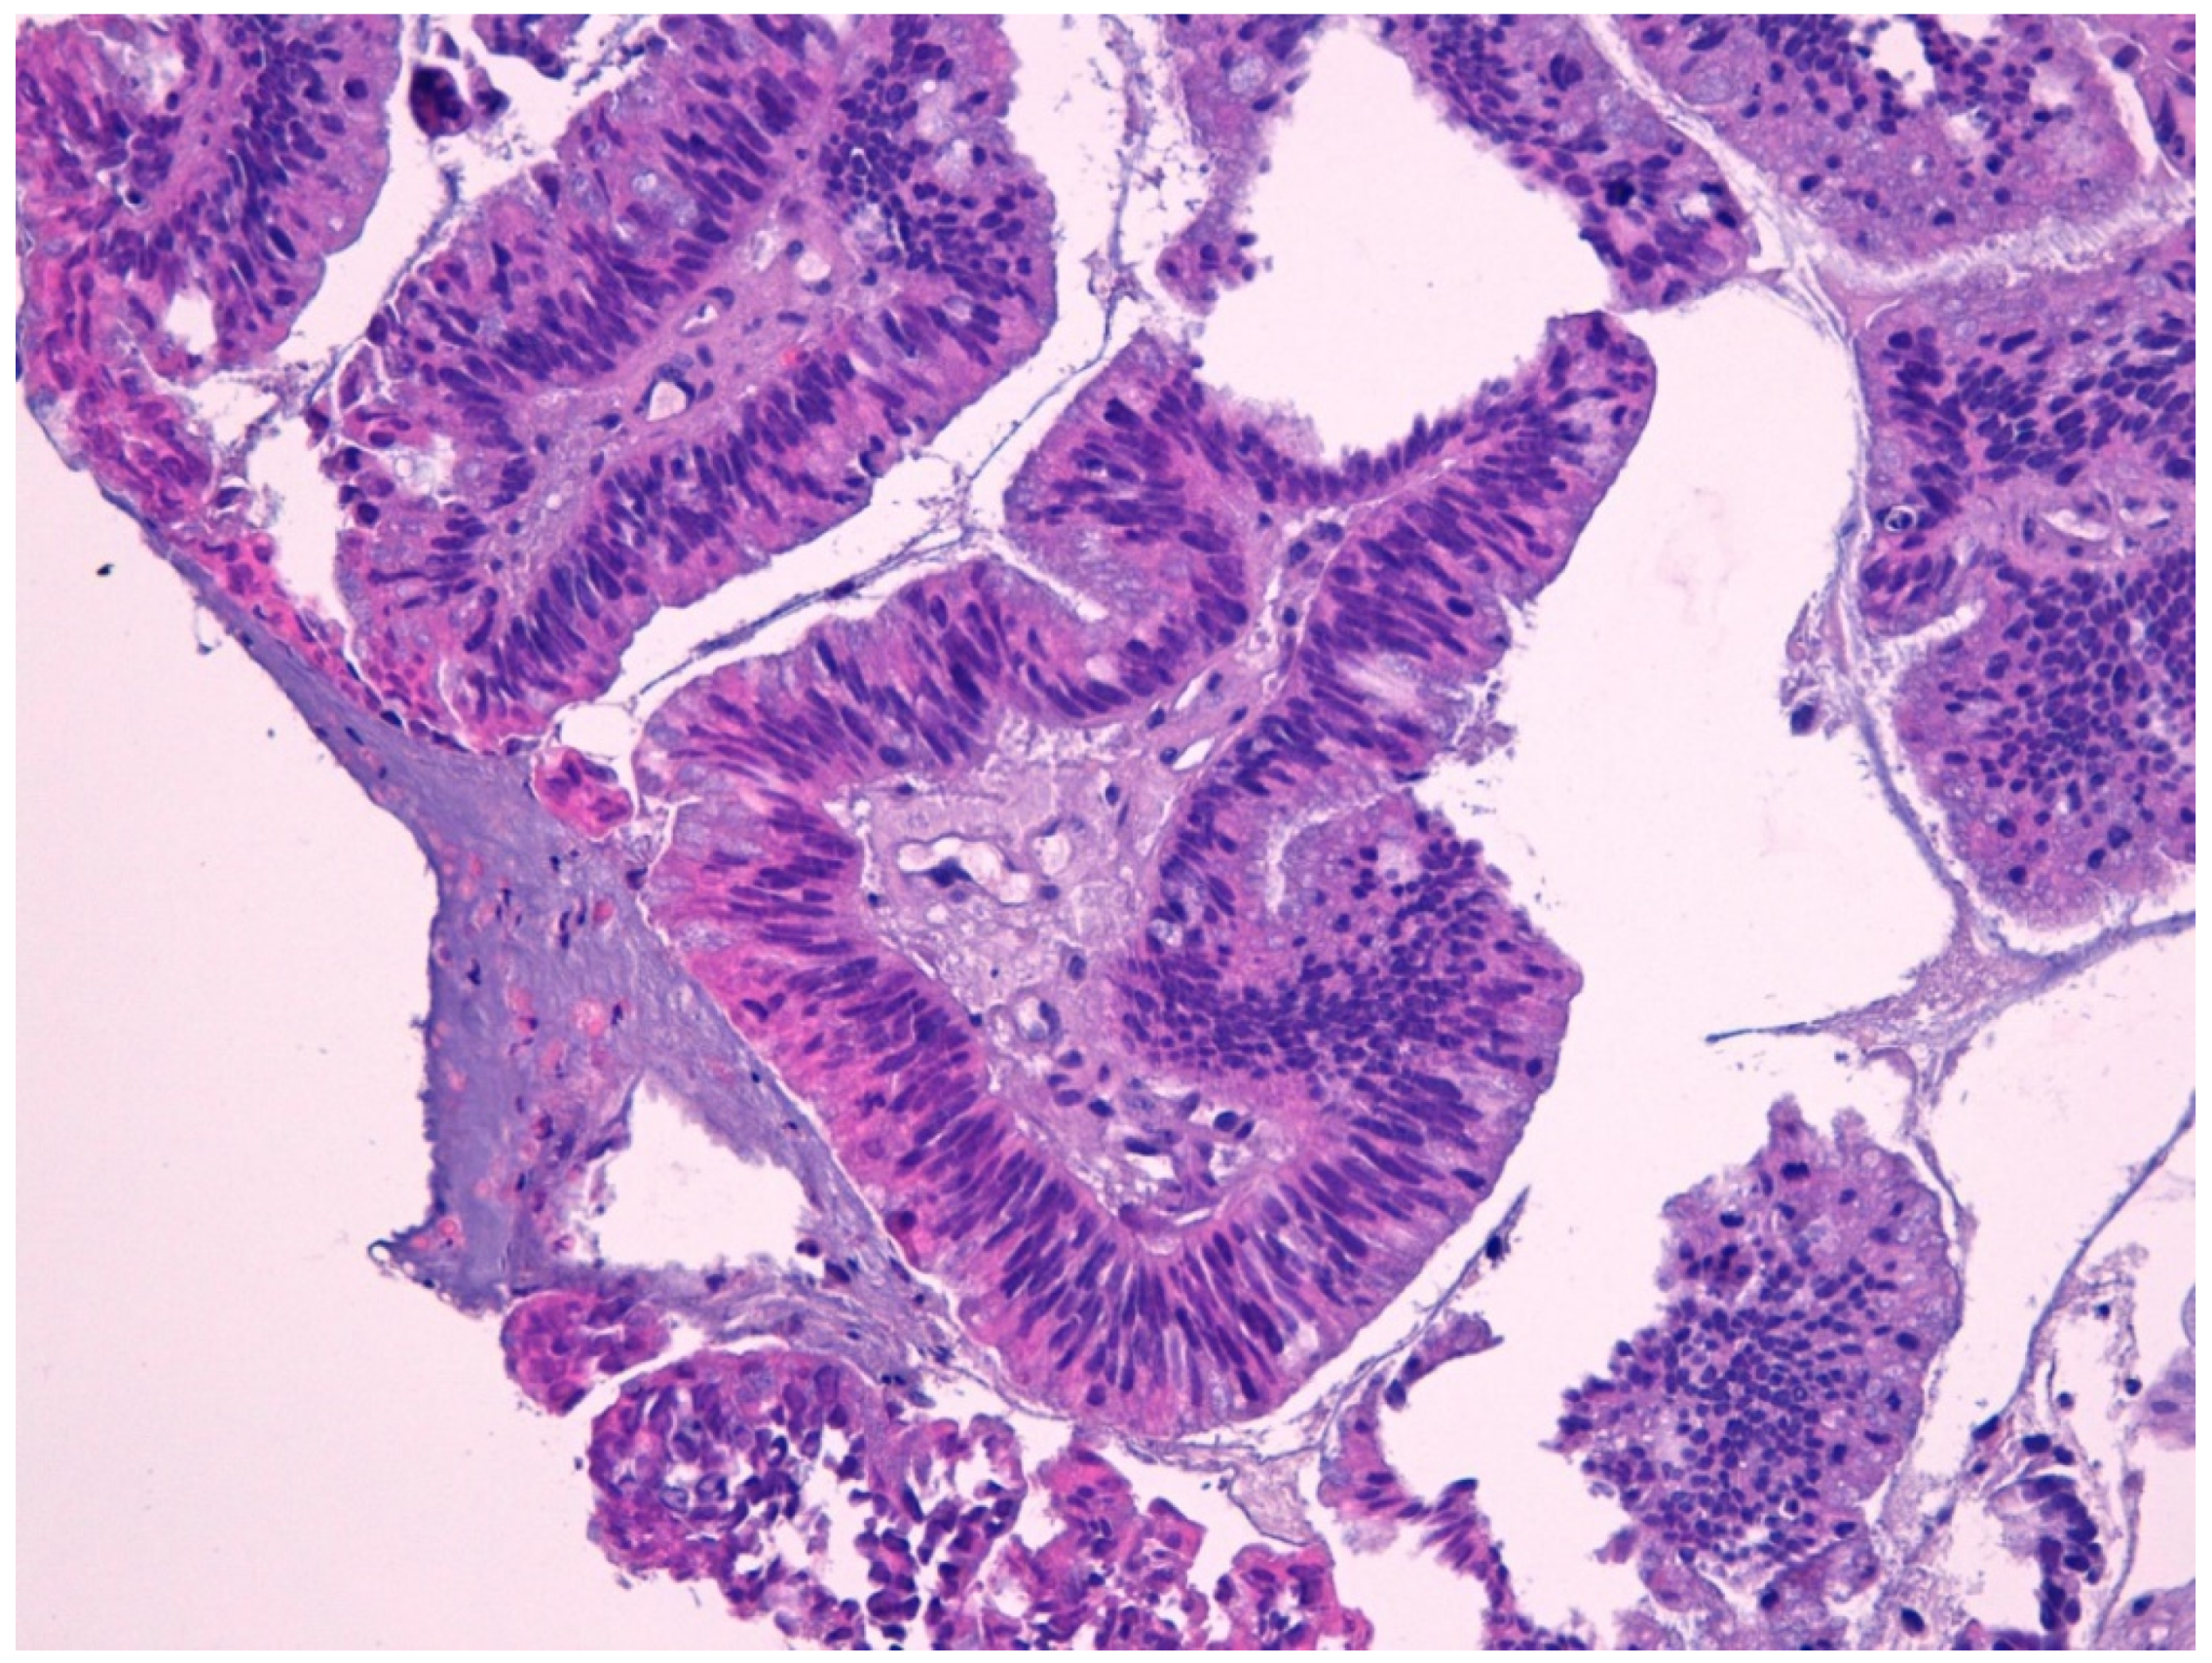

4.5. Intestinal Adenocarcinoma

- Franchi, A.; Gallo, O.; Santucci, M. Clinical relevance of the histological classification of sinonasal intestinal-type adenocarcinomas. Hum. Pathol. 1999, 30, 1140–1145. [Google Scholar] [CrossRef]